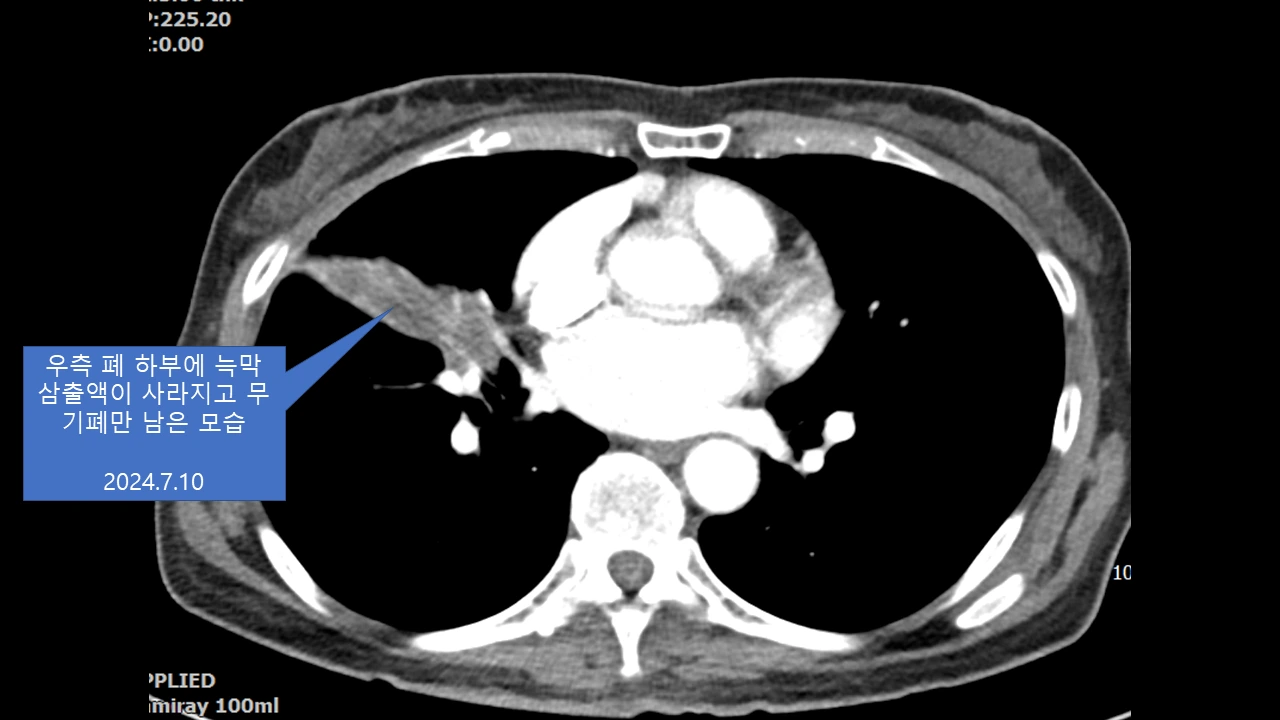

아래 또 다른 폐암 4기 환우분의 스토리도 너무 감동이라... 의사 선생님이 쓰신 글을 허락 없이 퍼왔다.